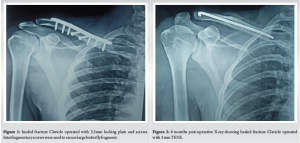

The fracture site was exposed as described above. The fracture was reduced using pointed reduction forceps. Then a 3.5 mm reconstruction plate is contoured to the shape of the clavicle (not required if anatomical locking plate is used) and placed over the superior/anterior surface of the clavicle and held temporarily with a cocker forceps or bone clamps in such a way that at least three holes were present on either side of the fracture. Then, drill holes were made using 2.5 mm drill bit, tapped using 3.5 mm tap and 3.5 mm cortical screws were driven to hold both cortices. Any loose fragments present were repositioned in its place and secured with encirclage wires or interfragmentary screw if needed (Fig. 1). A periosteal elevator was placed posterio-inferiorly to prevent penetration of the drill into deeper structures. The muscle and subcutaneous tissue were sutured over a suction drain. Skin closed with Ethilon no.3-0.

52 (55.32%) out of 94 patients were treated by conservative methods, and 42 (44.68%) were treated by surgical intervention. In that 15 (15.96%) patients were treated by ORIF or closed reduction and internal fixation with titanium elastic intramedullary nail. Notably, 2 cases of fractures treated with TENS required open reduction due to inadequate alignment and difficult closed reduction (Fig. 1). 27(28.72%) cases were treated by ORIF with 3.5 mm plate and screws. The mean follow-up was 8.2 months, ranging from 6 to 13 months. One of our cases of clavicle fracture operated by closed TENS, showed good fracture healing at 6 months (Fig. 2).